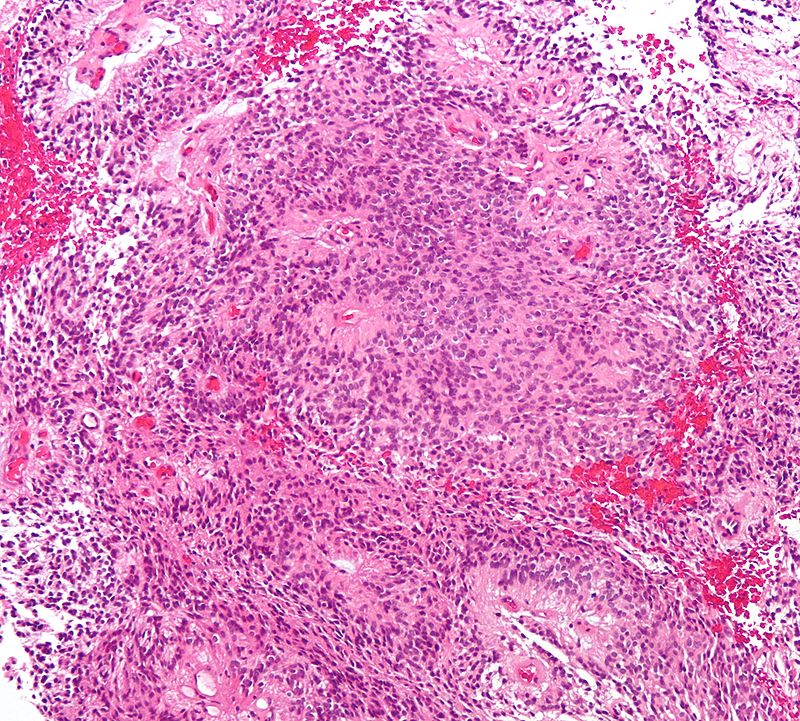

The histology of medulloblastomas shows small, rounded blue cells are visible on histology, and Homer-Wright rosettes might be present.